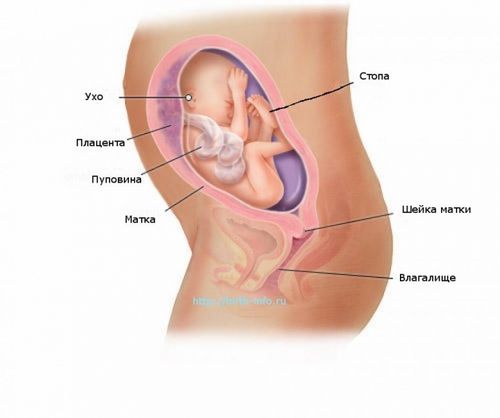

Матка вже розміром з футбольний м'яч. На огляді у гінеколога вам виміряють висоту стояння матки. Цей показник вже повинен досягати 25-27 сантиметрів. Тренувальні сутички Брекстона Хікса часто лякають майбутніх мам, особливо, якщо це їх перша дитина. Помилкові сутички ніяким чином не впливають на шийку матки, в той час як при справжніх сутичках шийка матки починає розкриватися.

Матка піднялася над лоном вже на 25 см, вона стала розміром у футбольний м'яч і здавлює інші органи. Малюк вже значно підріс, і тепер нерідко приймає положення «вприся мамі в ребра». Хоч характерно це патологічний стан частіше для більш пізніх строків вагітності, проте, перші його «відгомони» можуть даватися взнаки вже зараз.

Матка піднялася високо і підпирає діафрагму. Часи стає важче дихати, з'являється біль в ребрах, печія. Прекрасний час, щоб розставити пріоритети в житті, примиритися, і розпрощатися зі старими проблемами. Адже коли малюк народитися, йому потрібна буде щаслива, впевнена мама. Мама, яка готова брати на себе відповідальність, захищати і любити, що б не трапилося.